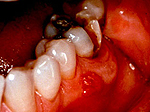

гострий періодонтит проявляється гострим зубним болем , При перкусії біль посилюється. Відзначається припухлість губи і щік; на яснах утворюється болючий набряклий інфільтрат, іноді відзначається патологічна рухливість зуба. У пацієнтів з гострим періодонтитом відзначаються загальні симптоми запалення: субфебрильна температура тіла і збільшення підщелепних лімфовузлів .

Хронічний перебіг періодонтиту має змащену клінічну картину і протікає мляво. Основними симптомами є відчуття незручності під час їжі і неприємний запах з рота. при хронічному періодонтит іноді з'являються свищі на яснах і на шкірі обличчя. Періодонтит виникає або в каріозної порожнини, або в опломбованому зубі, часто рецидивує, внаслідок чого пульпа некротизована.